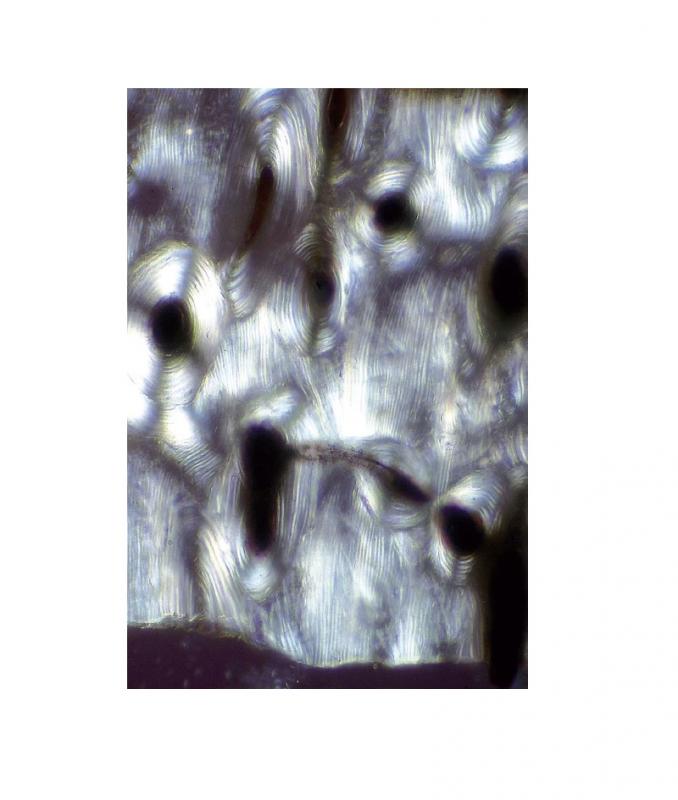

Préparation microscopique: Glycogène du foie

Glycogène dans le foie Préparation microscopique - Biologie animale - Cythologie et histologies diverses À l'unité